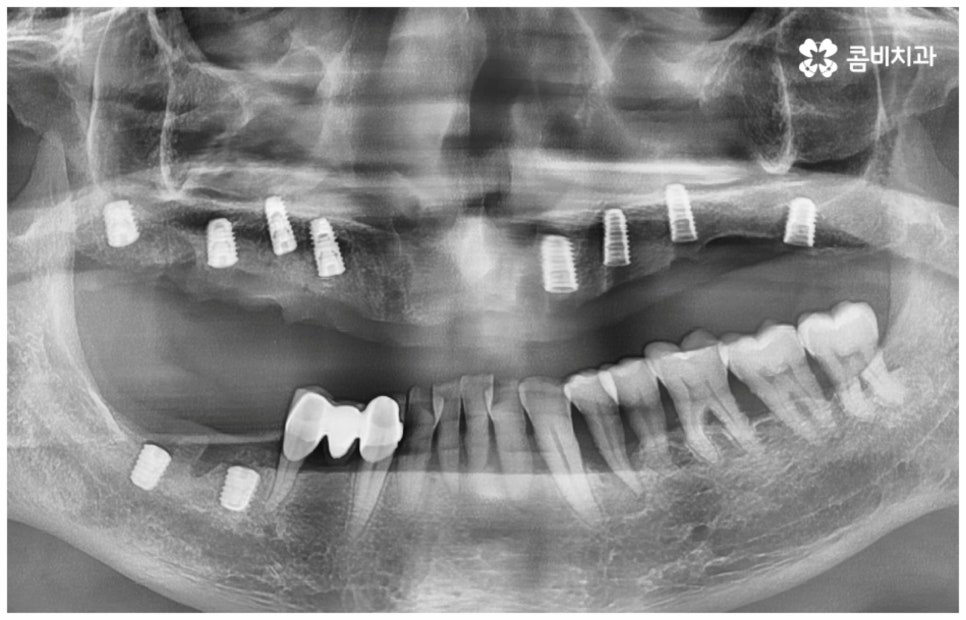

그러나 노화나 구강 질환을 원인으로 한 경우에는 식립 절차가 좀 더 복잡해 질 수 있는데요. 잇몸병을 예로 들어 생각해 보면 자연스러운 노화 및 관리 소홀로 인해 치아 주변 조직 (잇몸, 치주인대, 치조골 등) 에 염증 반응이 생기는 병인 치주 질환이 많이 심해졌을 때 상황에 따라 해당 자연 치아를 살리지 못하고 발치를 해야할 수도 있는 거예요. 이렇게 치주질환을 이유로 임플란트 식립을 진행할 때에는 식립 성공률을 높이고 임플란트수명 을 늘리기 위해 먼저 치주질환 치료를 선행해 줘야 하며, 환자분들의 상황에 따라 뼈이식 또는 상악동 거상술을 통해 잇몸뼈를 보충해 줘야 할 수도 있어요. 치조골이 이미 많이 녹아 있거나 병증이 극심하다면 임플란트 식립 난이도가 매우 높아지거나 때로는 불가능해 질 수 있기 때문에 다양한 임상 경험을 통해 풍부한 노하우를 가지고 있는 의료진에게 진단 및 치료를 받는 것이 굉장히 중요한 포인트라고 할 수 있습니다.

보통 정확한 위치에 식립하고 철저하게 사후 관리를 해 준다면 임플란트수명 은 거의 반영구적이라고 할 정도로 오랫동안 건강하게 사용할 수 있습니다. 그러기 위해서는 처음 식립할 때 환자분들의 상황에 맞게 체계적인 계획을 세워 정밀한 식립을 진행할 수 있는 시술자의 높은 숙련도 외에도 꼼꼼한 검사를 위한 3D-CT 와 같은 정밀 진단 장비를 갖추고 있는지 여부를 살펴보실 필요가 있어요. 이를 통해 환자분들 각각의 구강 구조, 치조골 상태 (밀도나 두께 등), 신경이나 혈관과 같은 주변 조직 등을 정확하게 분석한 다음 오랜 임상데이터를 바탕으로 높은 성공률을 보이고 있는 정품 재료를 사용하여 식립을 진행하는 것이 임플란트수명 을 늘리는데 도움을 주므로 이런 점들 역시 신경써서 살펴보시길 권유드리고 있습니다.